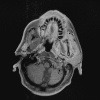

The anatomy of the jugular foramen is complex. It contains the lower cranial nerves and major vascular structures. Tumors that develop within it, or extend into it, provide significant diagnostic and surgical challenges. In this article, we describe the anatomy of the jugular foramen and outline an imaging protocol that can differentiate between lesions, thereby aiding diagnosis and facilitating management.